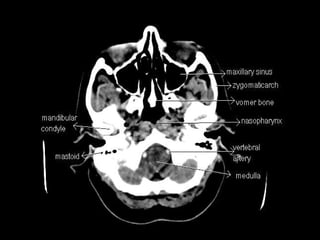

Radiographers use medical imaging equipment like X-rays and MRIs to produce images of patients' internal structures and organs. They are responsible for positioning patients, operating scanning machines, and ensuring quality images. Radiographers must have strong attention to detail, excellent communication skills, and the ability to work well under pressure to accurately capture anatomical features and diagnose any abnormalities.